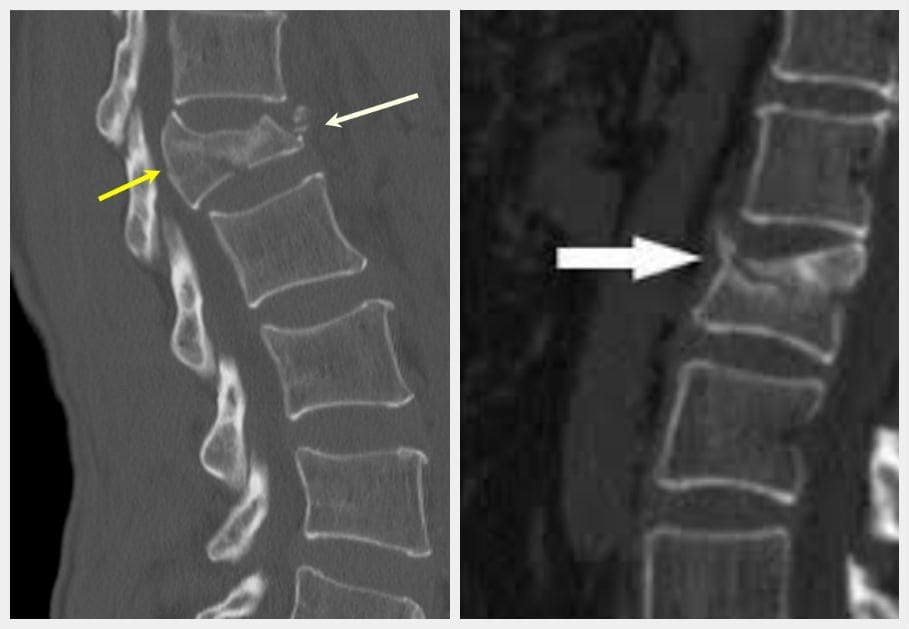

Рентгенография проводится для более детального обследования грудных, шейных, поясничных позвонков и дифференциации остеопороза от системных воспалительных или дегенеративно-дистрофических заболеваний. КТ позволяет оценить в динамике состояние соединительнотканных структур, расположенных возле деформированных позвонков.